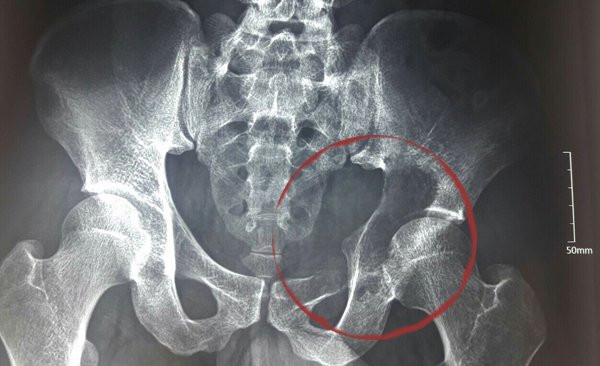

| Khối u kích cỡ lớn phá huỷ ổ cối và xâm lấn cả vào ổ bụng |

Sau khám, các bác sĩ BV K định có một khối u ở vùng ổ cối xương chậu, phá huỷ hoàn toàn ổ cối và phát triển vào ổ bụng bệnh nhân với kích cỡ khoảng 10cm, là u tế bào khổng lồ.